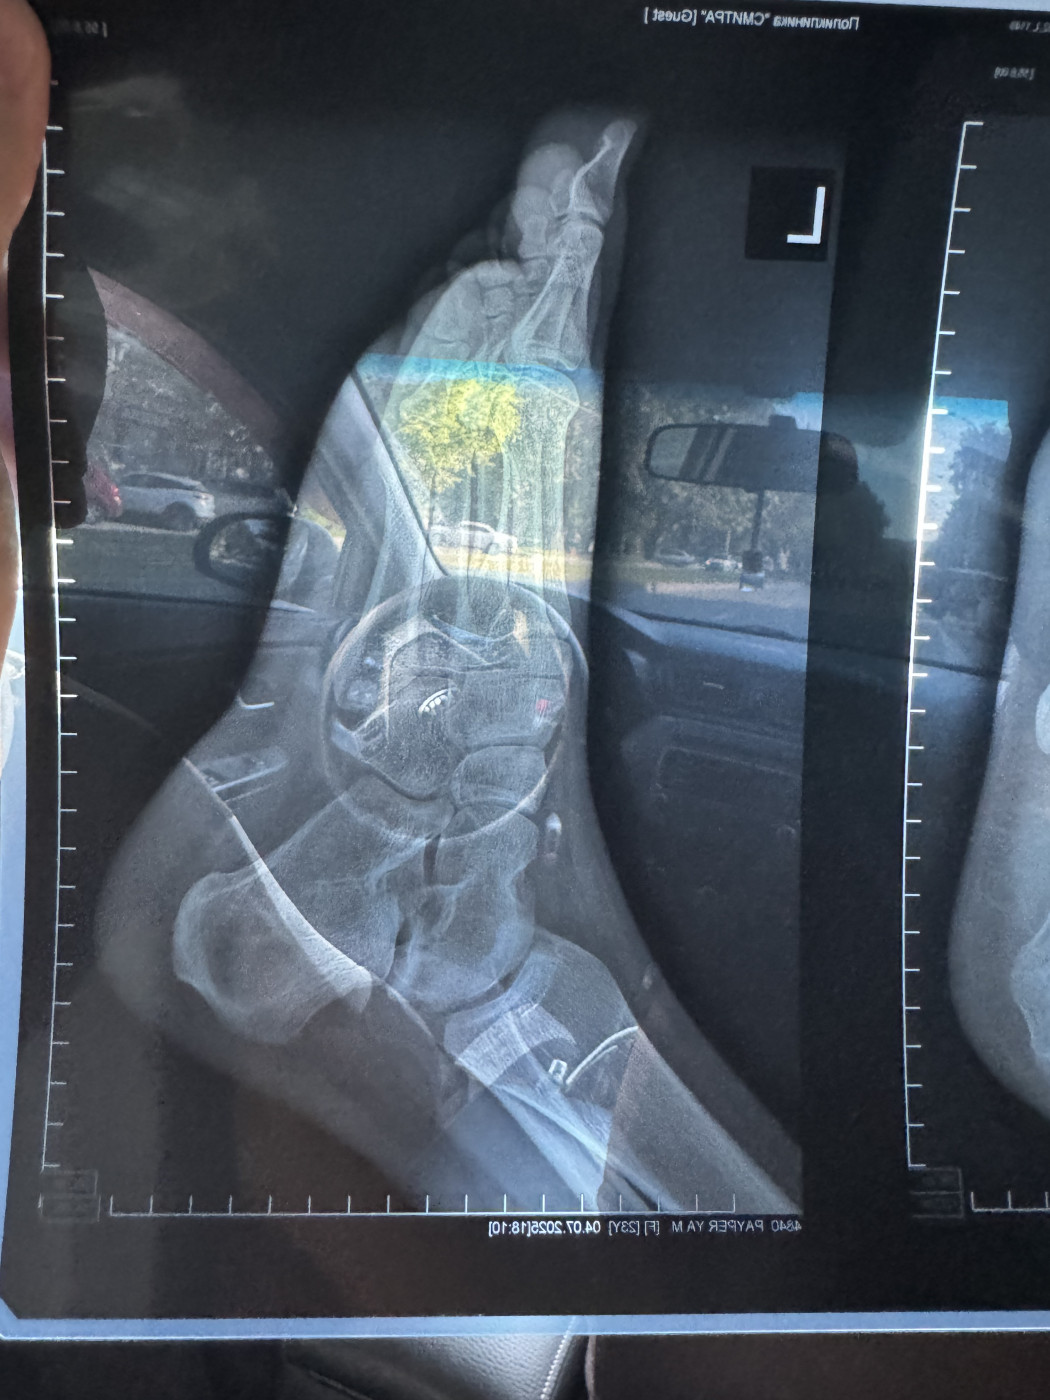

Пятка и остеопороз   1 ответ

Здравствуйте, сломала пятку10.06 , сегодня 25.07 сделала новый ренген

В травматологу могу попасть только в августе

Хотела бы узнать рекомендации сейчас